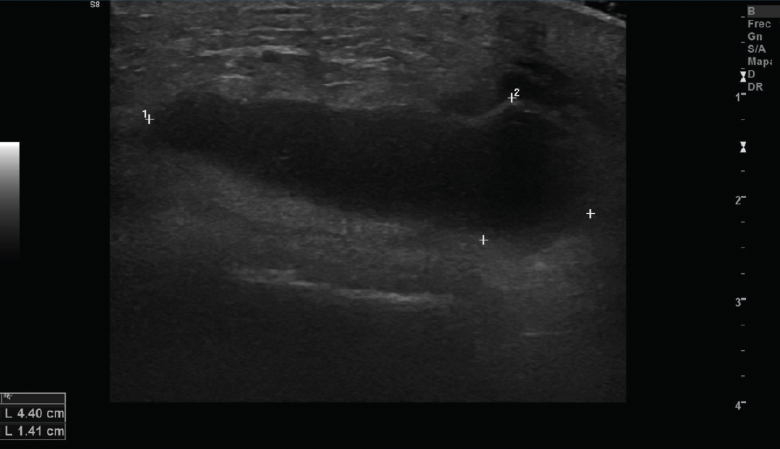

Se observan áreas hipoecoicas de solución de continuidad de las fibras tendinosas(7), con retracción de los márgenes con la contracción muscular cuando la rotura tendinosa es completa (Figuras 9 y 10).

Figura 9. Corte sagital de una ecografía de rodilla: foco hipoecoico por rotura parcial del tendón cuadricipital.

Figura 10. Corte sagital de una ecografía de rodilla: ausencia del tendón rotuliano por rotura completa, con hematoma señalado en el trayecto del tendón.

2.2. Roturas